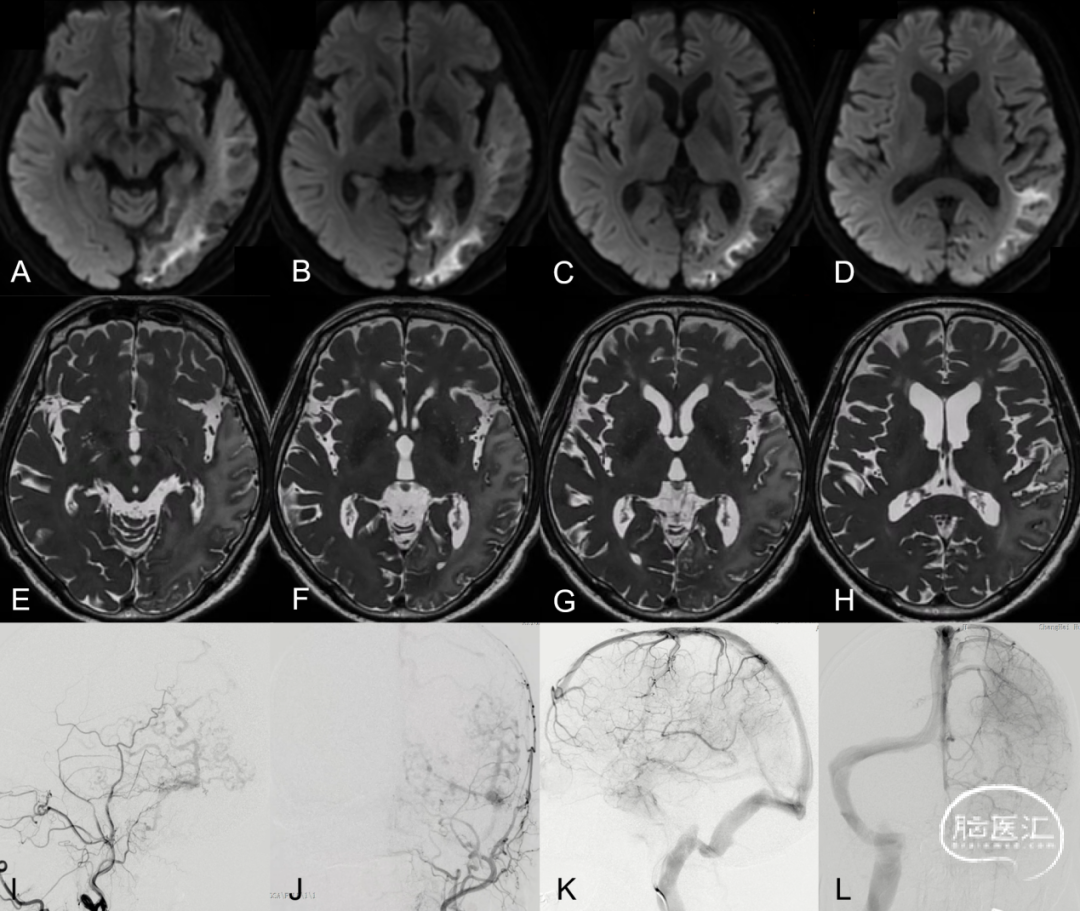

TOF-MRA是筛查和诊断DAVF并对DAVF进行分区定位的常用方法。DAVF的形态学特征包括供血动脉特点、瘘口部位、颅内静脉血栓形成等情况。识别DAVF血管构筑特点对于指导临床治疗具有非常重要的实用价值。有研究报道称TOF-MRA诊断DAVF的敏感性高达79.49% (95%置信区间CI: 66.81%–92.16%) ,特异性达100% (95%置信区间CI: 100.00%–100.00%) ,其主要诊断效力在于识别责任动脉及引流静脉。TOF-MRA原始图像具有较高的空间分辨率,对DAVF的关注点主要集中在瘘口复合体的基本形态,主要包括供血动脉、引流静脉、共同静脉端及逆流皮层静脉。

图7. 右侧枕动脉 (Occipital artery, OA) 参与DAVF供血,轴位最大信号投影 (Maximum intensity projection, MIP) 图发现右侧OA (箭头示) 较左侧OA (细箭示) 直径增宽、信号明显增强 (A) ;3D TOF血管重建,剪除周围血管后可以清晰显示右侧OA明显增粗 (B箭头示) ;右侧枕动脉造影证实右侧OA参与DAVF供血 (C箭头示)。左侧脑膜垂体干 (Meningo-hypophyseal trunk, MHT) 参与DAVF供血,轴位MIP图发现左侧MHT直径明显增宽、信号明显增强 (D箭头示) ;3D TOF血管重建清晰显示左侧MHT明显增粗 (E箭头示) 。左侧颈内动脉造影证实左侧MHT参与DAVF供血 (F箭头示) 。右侧脑膜后动脉 (Posterior meningeal artery, PMA) 参与DAVF供血,轴位MIP图发现右侧PMA直径明显增宽信号增强 (G箭头示) ;3D TOF血管重建显示右侧PMA明显增粗 (H箭头示) 。右侧椎动脉造影证实右侧PMA参与DAVF供血 (I箭头示) 。